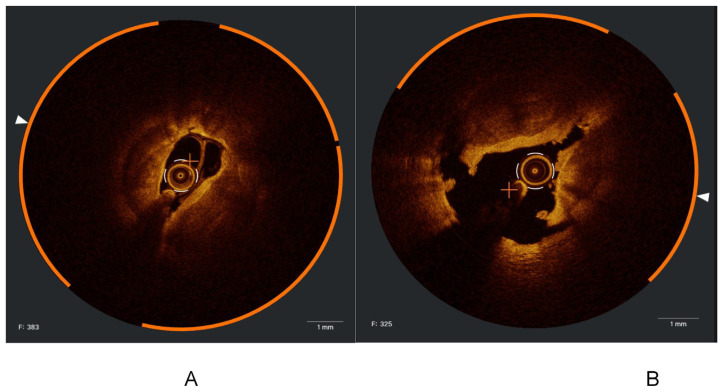

Abstract Image